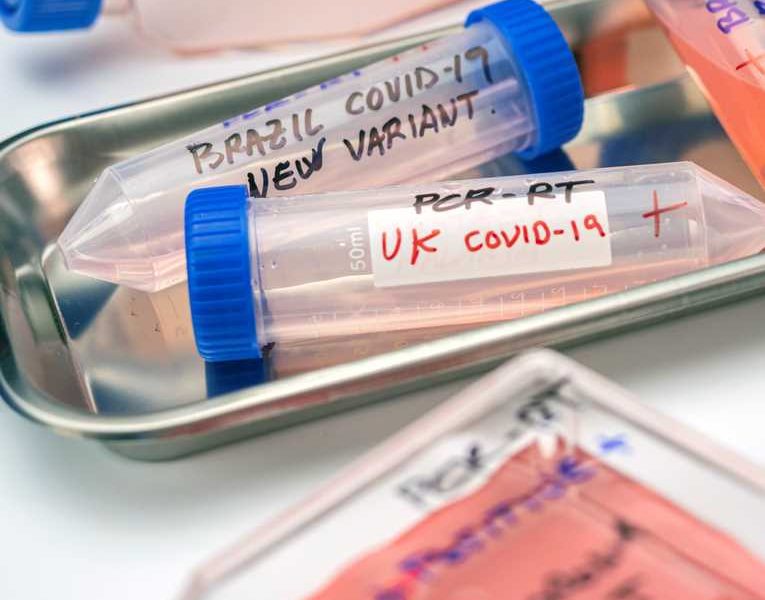

Po wariantach Alfa, Kappa i Delta koronawirusa teraz do Australii dotarł wariant Lambda – informują australijskie media. Wstępne badania sugerują, że nowy wariant może się szybko...

W Wielkiej Brytanii jest obecnie 25 wariantów koronawirusa, które są monitorowane i osiem dalszych pod szczegółową obserwacją - poinformowała w środę dyrektor rządowej agencji Public Health...

Nowy wariant koronawirusa z Indii spędza sen z powiek lekarzy i naukowców. Wiadomo już, jakie może dawać objawy.